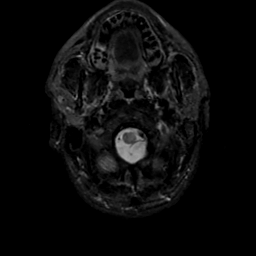

MR Study #17, July 7, 1991 -- Slice #2